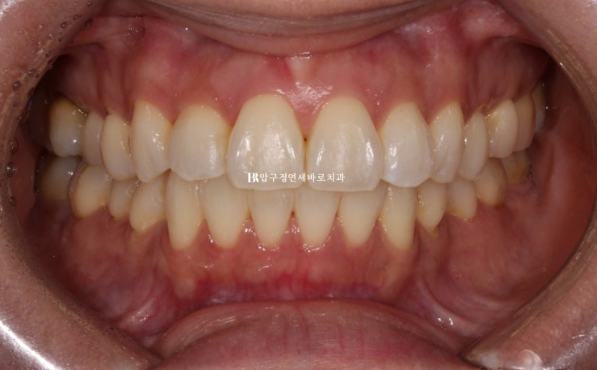

This is the appearance in the fourth month after treatment began.

Interproximal reduction was also performed for front-tooth alignment, and auxiliary appliances and elastic bands were used to eliminate the spaces that formed.

After 4 months of treatment, we finally completed treatment in January 2024.